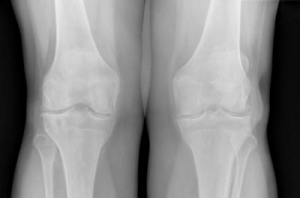

Arthrosebehandlung

Die Arthrose ist ein Verschleiß des Gelenkknorpels. Sie entwickelt sich normalerweise in der zweiten Lebenshälfte. Besonders häufig sind die Hüft- und Kniegelenke betroffen. Durch die verschlechterte Gleitfähigkeit der Gelenkpartner entstehen Schmerzen.